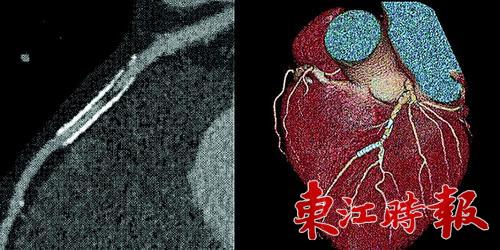

寶石能譜CT機火眼金睛查病因

近日,惠州市第三人民醫(yī)院引進了128層寶石能譜CT機。該CT機不僅克服了不少以往CT機的缺點,同時還有許多獨一無二的功能,代表著目前世界CT的先進水平,讓醫(yī)生的診斷更快更準(zhǔn)確,給患者帶來福音。

但是寶石能譜CT,卻可以不受金屬影響成影。不要小看這個功能,它帶來的卻是多種多樣的CT新應(yīng)用?;葜菔械谌嗣襻t(yī)院醫(yī)學(xué)影像科主任醫(yī)師崔冰告訴記者,有的冠心病患者曾植入過支架,有的骨頭受損傷的患者,身體內(nèi)植入了鋼釘,對面這些類型的患者,由于身體內(nèi)有金屬,再想通過常規(guī)CT來觀察是不太可能了,而磁共振也無法很好的解決這一問題。過去,醫(yī)生們只能用最為傳統(tǒng)的方法,了解病人恢復(fù)是否理想來判斷內(nèi)部情況?,F(xiàn)在使用寶石能譜CT,就可以通過成影直接看到患者植入鋼釘?shù)牟课?,如果出現(xiàn)問題,醫(yī)生能夠更加及時地發(fā)現(xiàn),并對患者加以治療。

“有一位60歲的患者,不愿開刀,就接受了寶石能譜CT檢測?!贝薇Q這位男性患者自稱胸悶,伴有其它病史,對插管較為抵觸。經(jīng)過寶石能譜CT檢測,醫(yī)生在該患者的動脈里發(fā)現(xiàn)血栓已有部分鈣化,并有管腔狹窄?!靶卵捎盟幬锟刂坪腿芩?,老血栓只能用支架撐開血管了?!贝薇硎?,常規(guī)CT只能顯示血栓,但是寶石能譜CT可以反映出新、老血栓,根據(jù)新舊的不同,采取的治療方法也不同。如今該患者的病很快就得到了確診,正在進行下一步的治療。